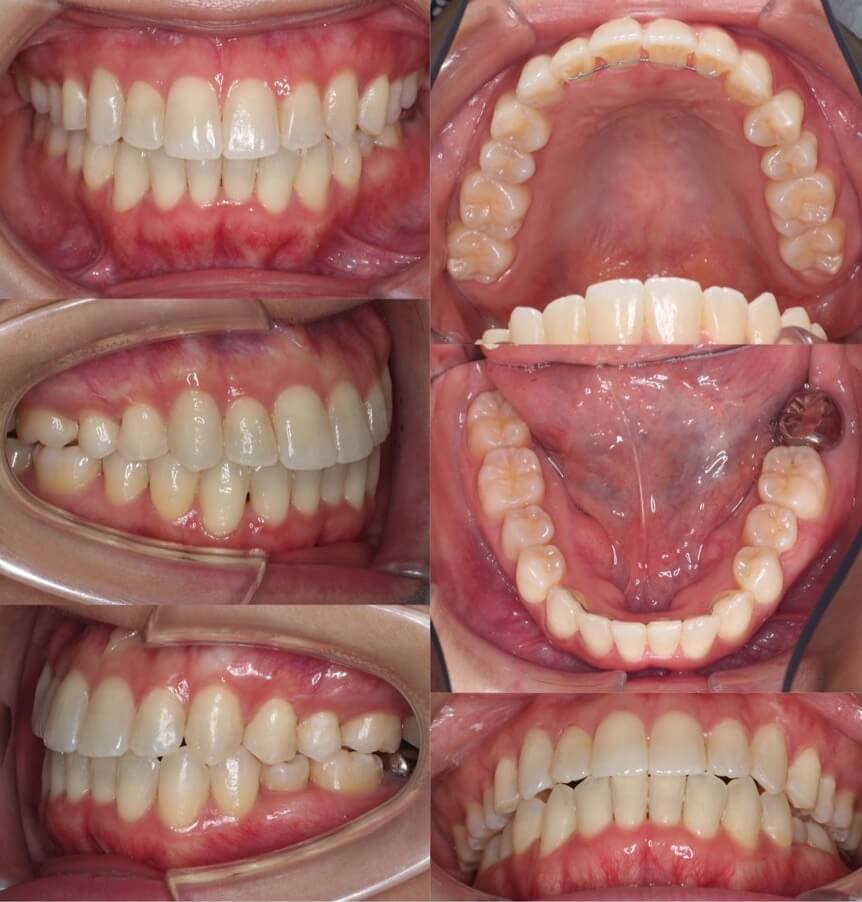

40歳女性・マウスピース型矯正装置

<症例概要>

主訴:クロスバイト

年齢・性別:41歳女性

住まい:千葉県浦安市

症状:下顎左偏・交叉咬合・上下顎前歯捻転・正中線の不一致

治療方針:右下臼歯後方移動・IPR・上顎歯列拡大

治療装置:マウスピース型矯正装置(アライナー装置)

治療期間:1年9か月

アライナー枚数:52+25+14(7日交換)

リテーナー:上下フィックスタイプ+クリアタイプ

治療費用:990,000(税込)

代表的副作用:痛み・治療後の後戻り・歯根吸収・歯髄壊死・歯肉退縮

下あごに非対称により奥歯のクロスバイトになっており、かみ合わせが安定していません。また、全体的にあ歯茎も下がってきています。矯正治療後は、歯茎に少し退縮がみられますが、上下の正中線は一致し前歯のかみ合わせは安定しました。